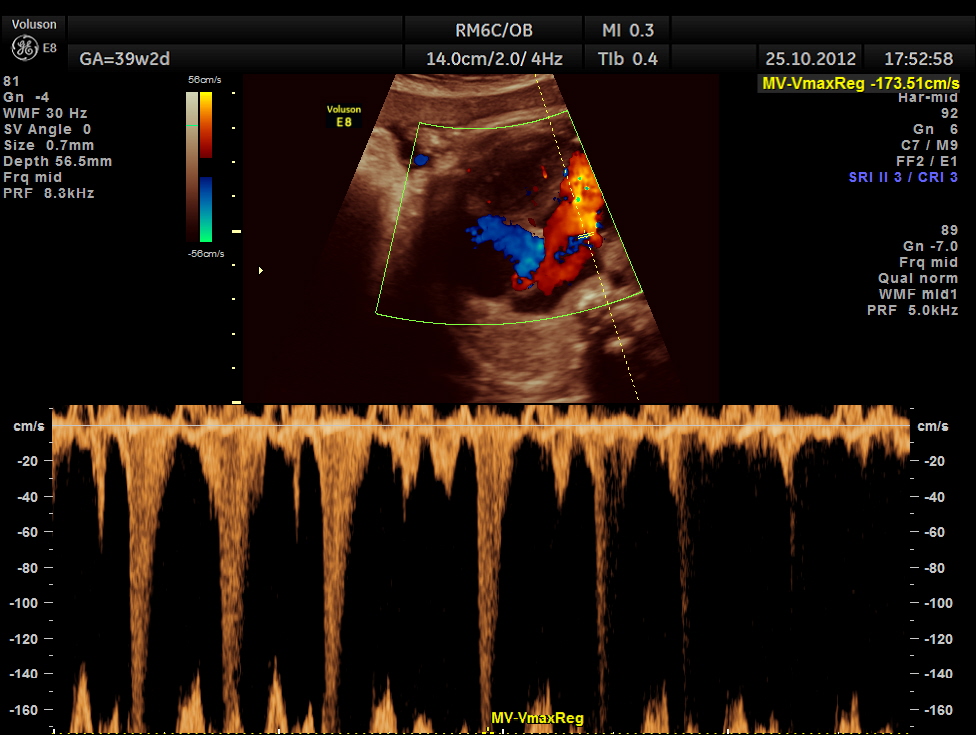

THIS FETUS HAD SEVERE FETAL ANEMIA WITH CARDIAC FAILURE LEADING TO CARDIOMEGALY WITH MITRAL, TRICUSPID AND PULMONARY REGURGITATION .NO OTHER OBVIOUS CARDIAC ANOMALY WAS MADE OUT . THE VENO ATRIAL , ATRIO VENTRICULAR AND VENTRICULO ARTERIAL CONCORDANCE APPEARED TO BE NORMAL; NO SEPTAL DEFECT WAS MADE OUT.